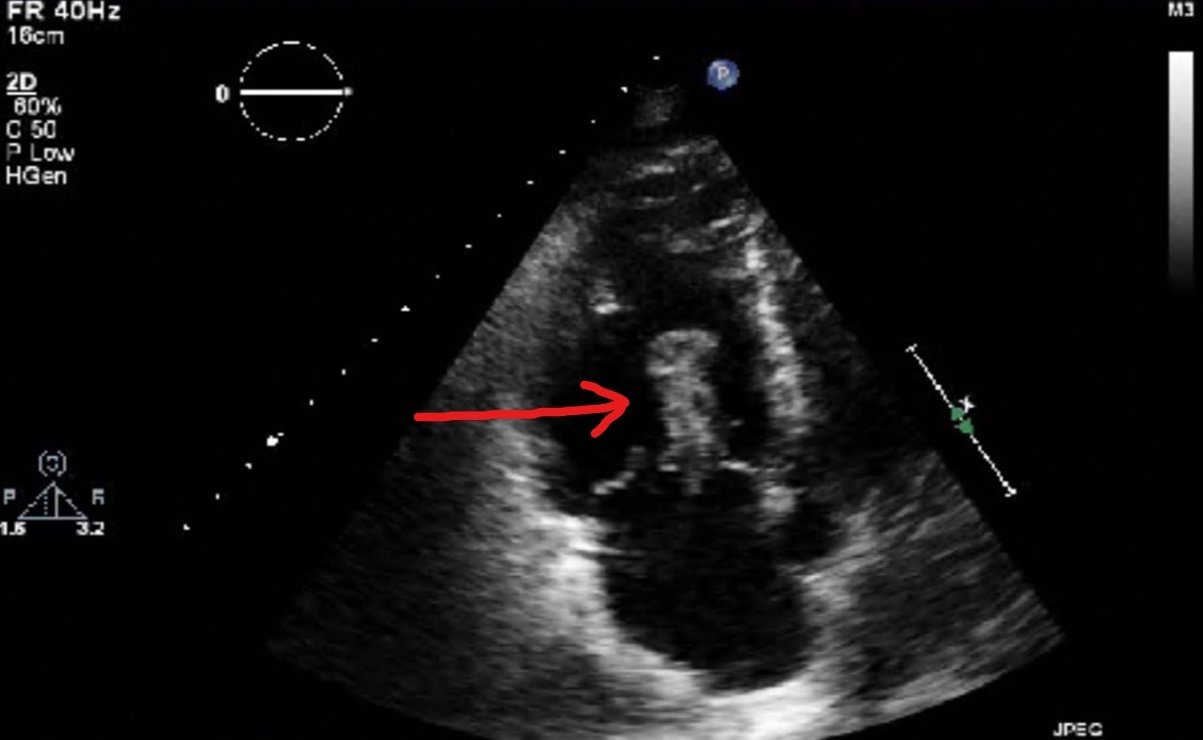

Bedside echocardiogram was performed, which revealed a free-floating thrombus in the right atrium on the sub-xiphoid view as seen in the video. The right atrium is denoted by the blue circle, in which a hyperechoic mobile mass can be seen. This finding was confirmed by an official echocardiogram which shows the thrombus in the right atrium extending through the tricuspid valve, as shown in the second image denoted by the red arrow. Significant right heart strain was also found, with severe pulmonary hypertension and intraventricular septal flattening.